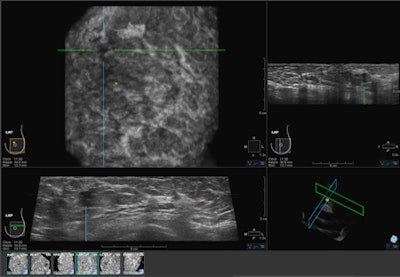

| ABUS image showing mass in upper-outer quadrant of the left breast. Image courtesy of U-Systems. |

Several studies on ABUS will be presented at the 2012 RSNA meeting, including one led by Dr. Rachel Brem of George Washington University Medical Center. Brem's study found that ABUS enabled detection of early-stage cancers in women with dense breasts, giving healthcare providers time to start early treatment. In all, 88% of cancers found by ABUS alone in a group of 15,000 women were grade 1 or 2.

Another study, to be presented by Maryellen Giger, PhD, of the University of Chicago, found that adding ABUS to mammography for women with dense breast tissue improved sensitivity by 23.3 percentage points, from 38.8% for mammography alone to 63.1% for mammography plus ABUS.